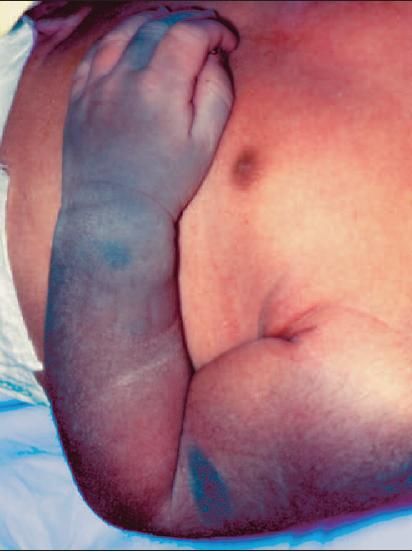

FigureThe bluish gray skin coloration of the left upper extremity, including the thumb and middle finger, and on the right buttock in a full-term, African American, newborn girl is congenital dermal melanosis.

This fairly common phenomenon, also known as Mongolian spots, affects more than 90% of African Americans, 80% of Asians, 46% of Hispanics, and fewer than 10% of Caucasians.1 The bluish gray or slate-colored areas occur most frequently on the lower back and buttocks and less frequently on the posterior thighs, legs, back, and shoulders. The face is rarely affected. The skin coloration is believed to be caused by melanocyte migration arrest from the neural crest to the epidermis.

In most cases, no treatment is necessary. Parents can be reassured that the condition is benign and that the affected areas (particularly in persons with dark skin) tend to fade or blend in with skin hyperpigmentation that increases naturally within the first few months or years of life. The pigmentation of less commonly involved areas is less likely to fade over time.2 Malignant degeneration has not been reported.1

Of chief concern is the possible misdiagnosis of bruising in the infant or child with these lesions, which can lead to allegations or suspicion of child abuse. It is important to document (with photographs at birth and/or other methods) the location, size, and shape of congenital dermal melanosis when observed in newborn babies to prevent wrongful accusations of caregivers.